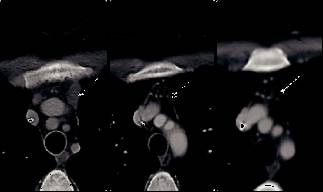

治疗1个月奇迹出现了,CT显示M女士纵隔淋巴结肿大缩小,没有新的肝或纵隔病变(图1A和B和2A和B与图1C和2C),并且在3个月时的影像学检查显示出纵隔淋巴结肿大和肝脏局部病变进一步缓解(图1D和2D)。8个月的影像显示纵隔淋巴结持续缩小,肝脏病变完全消退(图1E和2E)。患者目前仍继续进行治疗。

图2:ABCDE